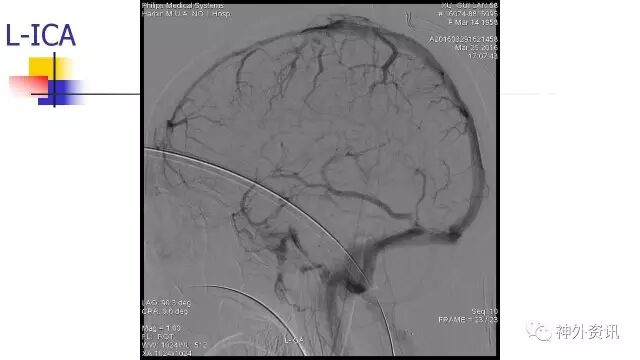

L-ICA正位动态